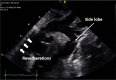

Cardiac ultrasound techniques are increasingly used in the neonatal intensive care unit to guide cardiorespiratory care of the sick newborn. This is the first in a series of eight review articles discussing the current status of "neonatologist-performed echocardiography" (NPE). The aim of this introductory review is to discuss four key elements of NPE. Indications for scanning are summarized to give the neonatologist with echocardiography skills a clear scope of practice. The fundamental physics of ultrasound are explained to allow for image optimization and avoid erroneous conclusions from artifacts. To ensure patient safety during echocardiography recommendations are given to prevent cardiorespiratory instability, hypothermia, infection, and skin lesions. A structured approach to echocardiography, with the same standard views acquired in the same sequence at each scan, is suggested in order to ensure that the neonatologist confirms normal structural anatomy or acquires the necessary images for a pediatric cardiologist to do so when reviewing the scan.